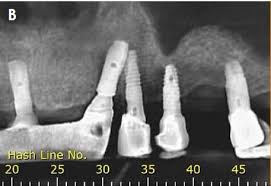

It is used to plan treatment for dental implants, check for impacted wisdom teeth and detect jaw problems.

1 . Intraoral,

Extraoral.

Each type serves specifice diagnostic purpose and provides different views of the mouth’s internal structures.